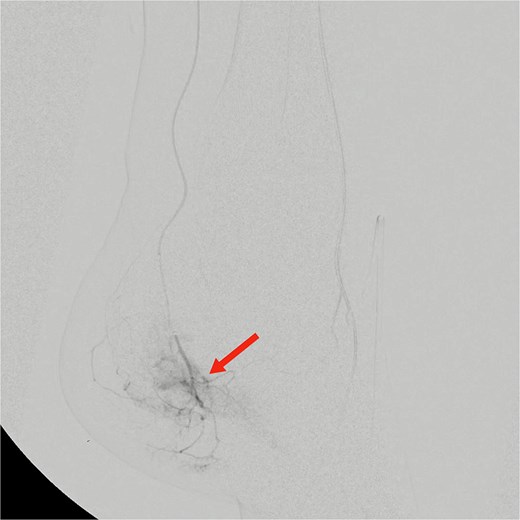

Given the refractory symptoms, TAE was planned. Under ultrasound guidance, the left dorsalis pedis artery was accessed retrogradely using a 5 Fr Cordis Rainsheath sheath (20 cm). After heparin administration, diagnostic angiography revealed patent anterior, posterior tibial, peroneal, and popliteal arteries. The tibioperoneal trunk was selected from the anterior tibial artery using a mini Rim catheter, followed by distal posterior tibial artery selection. Foot angiography demonstrated a prominent hypervascular blush in a branch of the medial plantar artery (Fig. 1).

Pre-embolization digital subtraction angiography showing prominent hypervascular blush in branches of the medial plantar artery arising from the distal posterior tibial artery (arrow).